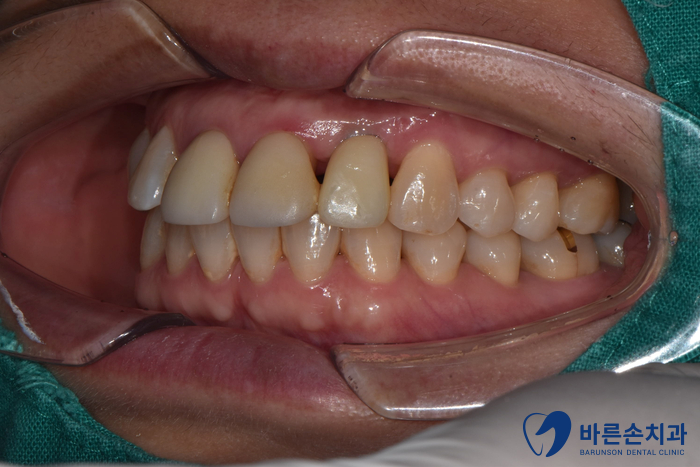

After 25.09.09

상실된 어금니와 함께

앞니 임플란트가 완료 되었습니다. !

정상적인 위치에 자리잡은 치아가 보이시나요?!

원래 내 치아처럼 회복되었습니다!

앞니 부분 잇몸이 크게 내려가지 않아,

주변 치아들과 이질감이 없습니다.